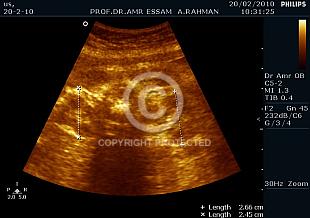

Can you guess fetal gender?

Fetal gender identification

Fetal Gender